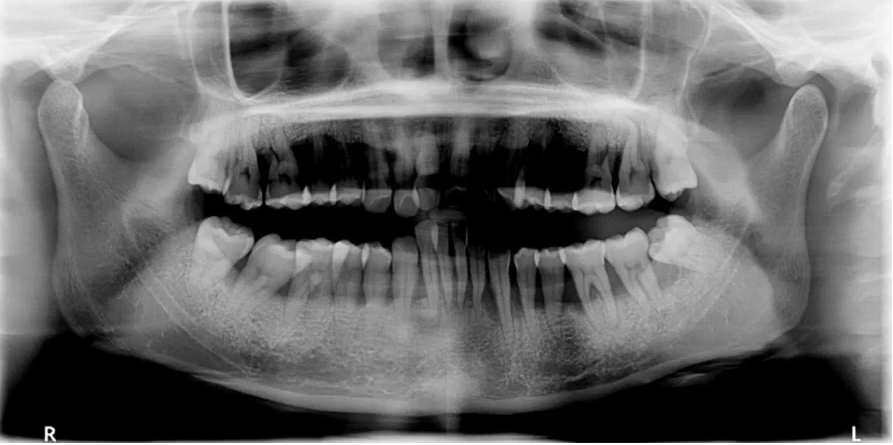

口腔曲面断层X线摄影(Rotational Panoramic Radiography)通过专门设计的口腔曲面全景摄影X线机,将上颌骨、下颌骨、颞颌关节、上颌窦、鼻腔及全口牙齿的影像同时显示在1张体层照片上的摄影技术。

口腔曲面断层摄影在医疗诊断中德应用越来越广泛,它能为牙科病,牙齿矫形以及牙槽骨,题颌关节的骨折骨病等多种疾病提供重要的信息。

一、理想曲断影像

中线左右对称,牙齿排列呈微笑弧形,片子左右两边相对对称,能清晰显示颞下颌关节、上下牙列的牙根,图像的对比度和分辨率较好。

二、曲面断层片的用途

1. 全面显示牙列:牙体疾病初步诊断

比如下面这张片子显示出的龋坏合并根尖周炎。

三、曲面断层片

(一)解读

1. 先整体后局部,有顺序不遗漏

因为曲面断层片反映的是上下颌牙齿、上颌窦、关节,在一张片子中所展示的解剖结构较多。比如刚才的片子,最容易诊断的是右下6远中邻面深龋合并根尖周炎,左下有埋伏的多生智齿,右侧是垂直智齿。

注意不要遗漏,比如片子中显示上颌两个3是缺失的,是先天性缺失还是做过手术?有可能会漏掉一些临床信息。

2. 推荐象限顺序

1(右上)→2(左上)→3(左下)→4(右下)

3. 推荐检查部位顺序

牙→骨→上颌窦→关节

比如患者右侧髁突的前斜面发生了硬骨改变。

4. 左右对称比较

左、右下5根方有低密度影,一般认为是颏孔位置,左右对称进行观察可以排除一些疾患。